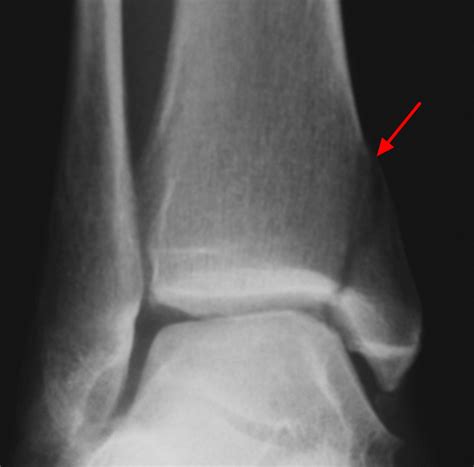

X-Rays

X-rays are often the first line of imaging for ankle injuries. They can help identify fractures, dislocations, and other bony abnormalities. However, X-rays may not always show soft tissue injuries, such as ligament tears.